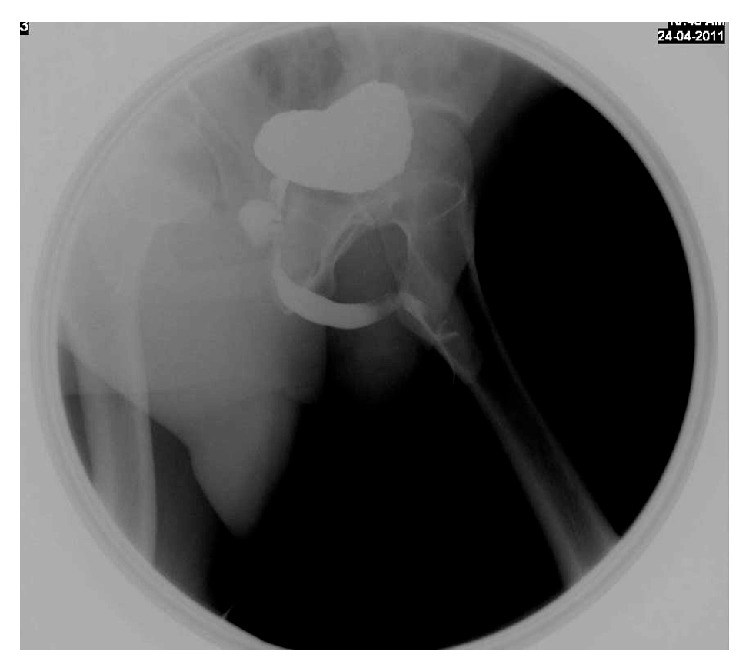

Cowper's gland syringocele is an uncommon, underdiagnosed cystic dilatation of Cowper's gland ducts showing various radiological patterns. Herein we report a rare case of giant Cowper's gland syringocele in an adult male patient, with description of MRI findings and management outcome.